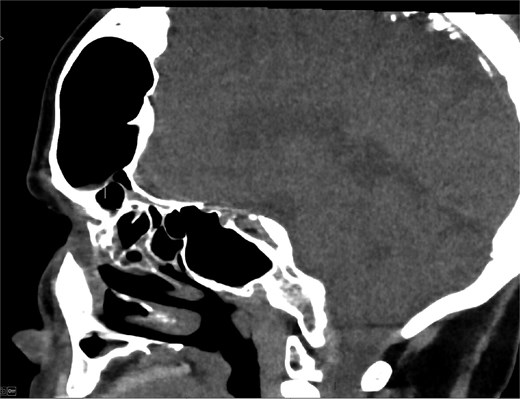

MRI demonstrated marked expansion of the left frontal sinus, consistent with PD, exerting a mass effect on the adjacent left frontal lobe and associated with a small area of increased T2-FLAIR signal intensity (Fig. 1). There was no evidence of compression of the lateral ventricle. However, mild prominence of the sulci and lateral ventricle on the left side suggested underlying parenchymal volume loss. No signs of hydrocephalus, midline shift, restricted diffusion, or susceptibility artifacts were identified. The optic nerve, optic chiasm, and optic tracts appeared normal. CT tomography confirmed these findings (Figs 2 and 3).

CT scan axial view showing hyperaeration of the left frontal sinus.